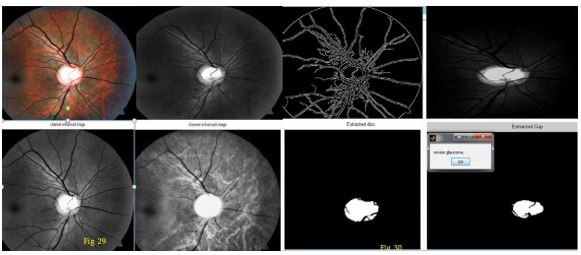

Severe stage

Figure 14: Showing severe stage Glaucoma.

In above figure 14 we can observe all steps of glaucoma image processing. After processing on image we can see cup extracted image and disk extracted image. In above figure we can Cleary see increase in size of cup and disk. That is symptom of severe glaucoma. In above figure 14 we calculated cup to disk ration which is 0.5920.

According to condition if cup/disk > 0.55 then it is severe condition of glaucoma. In this patients image we find gluacoma symptom.

Figure 15: Severe stage Glaucoma with increase in cup size.

Figure 16: Showing severe stage Glaucoma with cup/ratio 0.5840.

In above figure 15 and 16 we can observe all steps of glaucoma image processing. After processing on image we can see cup extracted image and disk extracted image. In above figure we can Cleary see increase in size of cup and disk. This is symptom of severe glaucoma. In above figure we calculated cup to disk ration which is 0.5840.According to our condition, if cup/disk > 0.55 then it is severe condition of glaucoma. In this paitients image we find glaucoma symptom.